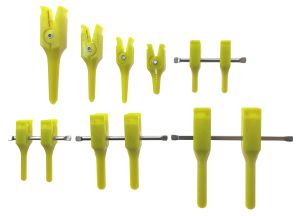

Πλαστική – Γναθοπροσωπική Χειρουργική

Λεπτομέρεια, λειτουργικότητα, αισθητική αρτιότητα

Με εξειδίκευση στις πλαστικές και γναθοπροσωπικές επεμβάσεις, παρέχουμε προηγμένα ιατρικά υλικά και τεχνολογικές λύσεις που ανταποκρίνονται στις υψηλές απαιτήσεις της επανορθωτικής χειρουργικής. Η πολυετής μας εμπειρία εγγυάται ποιότητα, ακρίβεια και αξιοπιστία σε κάθε στάδιο της χειρουργικής διαδικασίας.

Η εταιρεία μας, σε συνεργασία με κορυφαίους διεθνείς κατασκευαστές, διαθέτει στην ελληνική και κυπριακή αγορά εξειδικευμένα υλικά και εργαλεία, που ξεχωρίζουν για την ακρίβεια, τη βιοσυμβατότητα και το άρτιο αισθητικό τους αποτέλεσμα.

Στην κατηγορία Πλαστικη- Γναθοπροσωπική Χειρουργική, θα βρείτε επιλεγμένα προϊόντα υψηλής ποιότητας, σχεδιασμένα για:

• Μείωση του χρόνου επέμβασης

• Επιτάχυνση της διαδικασίας αναστόμωσης

• Ταχύτερη επούλωση, Λιγότερη Τάση, Βελτιωμένη Αισθητική

Δείτε αναλυτικά τα προϊόντα μας και ανακαλύψτε την ποιότητα που μας καθιστά αξιόπιστο συνεργάτη σε δημόσια νοσοκομεία και ιδιωτικές κλινικές